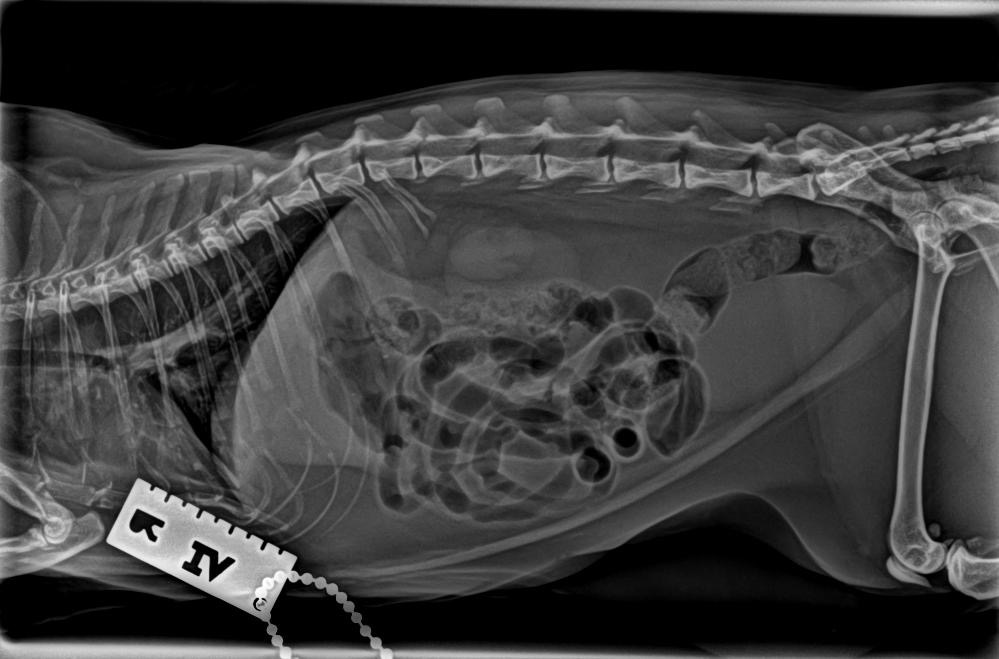

개구호흡과 컥컥거리는게 피토하는거보다 위험해보인다고 엑스레이를 찍자고하길래 찍었어요.

그런데 의사소견으로 폐에 물이 차 보인다는거에요. 당장 응급실로 가보라고...

17일 수요일아침... 9년동안 생전 설사는 한적도 없는녀석이

위장출혈로 의심되는 흑변을 본거에요.

그런데 마지막 구토후에... 애가 갑자기 휘청거리고 다리 힘이 빠지는거 같았어요...

15년 집사경험상 이건 진짜 위험한 사인이라,

놀란가슴 부여잡고 지체없이 바로 알아봐둔 응급실로 갔답니다....